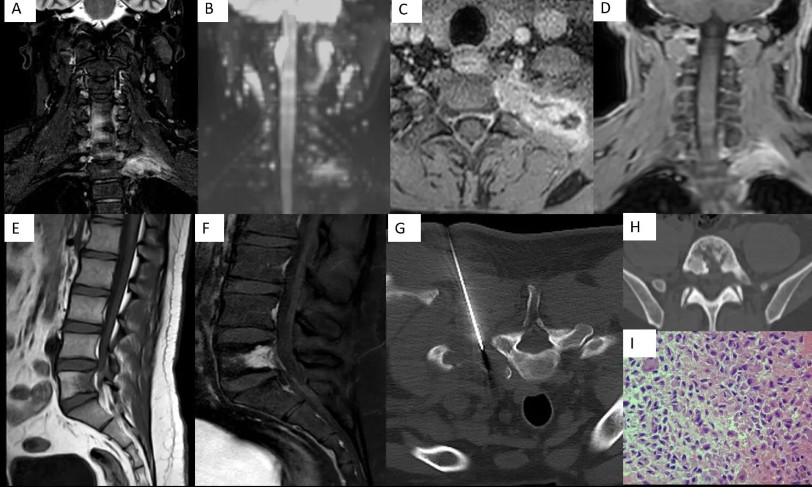

As people of science, the hunger to upskill never really settles — science, medicine, innovation, intervention. Ending 2025 with two ISNR Case of the Month offerings for the ever-curious neuroradiologist 🧠 isnr.in/december-2025-… isnr.in/december-2025-…

♦️ ISNR Case of the month ♦️ isnr.in/july-2025/ Thanks to the contributors Dr Rakesh @DrSmilySharma @drbejoy2002 @ Dr Kesavadas Share your interesting cases @ case.isnr@gmail.com to be featured in the case of the month platform of ISNR website